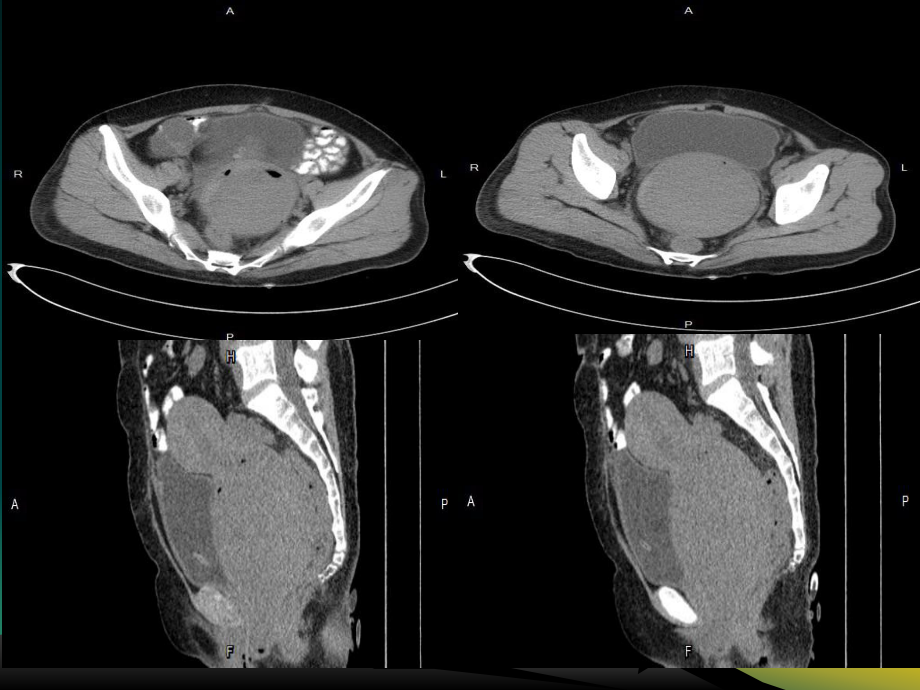

1、患者:张xx CT: 74698 性别:女年龄:42岁临床初步诊断:宫颈肿物主诉:既往抑郁病史6年,既往剖宫产史,平素月经史不规律,近半年阴道不规则流血,1天前自觉腹胀、排尿困难平扫动脉期静脉期延迟期 影像学诊断: 宫颈区软组织密度灶,考虑子宫肌瘤 右附件囊性低密度,请结合临床病理诊断: 全切子宫及双侧输卵管、宫颈肿物、右卵巢肿物 1.宫颈:富于细胞性平滑肌瘤伴玻璃样变性; 2.右卵巢:浆液性囊腺瘤; 3.增殖型子宫内膜; 4.双侧输尿管组织。临床诊断:宫颈粘膜下子宫肌瘤;右卵巢囊肿、失血性贫血术中图片: 子宫肌瘤: 子宫肌瘤是女性生殖系统最常见的良性肿瘤之一,由平滑肌和结缔组织组成; 病因:

3、样变:供血不足,部分组织水肿、漩涡结构消失,代以透明样物质 2.囊变:继发玻璃样变、液化坏死、液体清凉 3.红色样变:特殊肌瘤坏死,多发生产褥期或妊娠期,与局部组织缺血或栓塞所致组织出血、溶血有关,血液渗入肿瘤、生肉状; 4.肉瘤变性:恶性变;多见年龄大且生长快或伴不规则流血者、 5.钙化:多见瘤蒂细、供血不足浆膜下的肿瘤及绝经期肌瘤 CT:1.子宫均匀或分叶状增大,局灶密度减低和宫腔偏位,2.子宫肌瘤密度均匀,边界清晰,周围脂肪层存在,呈现良性肿瘤特征3.发生变性,肌瘤可呈等、低、高混杂密度。 优缺点:空间分辨率高,直观全面;分辨脂肪、出血、钙化成分上具有一定优势;缺点:对病变大小、数目、部

4、位缺乏特异性;判断肌瘤变性不敏感增强时子宫肌层和肿瘤一样显著强化,多数子宫肌瘤与正常子宫肌层密度差异不大,若无轮廓变化、小的肌瘤容易漏诊,病灶变性时,增强后不规则低密度区更为清楚,增强扫描有助于诊断及定性。MRI:1.子宫增大、轮廓凸凹不平;2.T1与子宫肌体相近、T2呈低信号,但伴坏死、液化出血等可呈高信号;3.肌瘤变性,不同病理改变,信号各异,钙化呈T1T2均呈低信号、脂肪变性则高信号;4.MRI组织分辨率高,T2可显示子宫肌层与内膜之间的结合带,呈低信号;粘膜下或肌壁间肌瘤可见结合带局灶中断或完全消失;此类病人大多数有月经过多表现;T2瘤周高信号环,常提示瘤周扩张静脉、淋巴管及水肿性改变,并常见较大肿瘤上的血管断面,T1、T2表现信号缺失区优缺点:对小肌瘤诊断率高,浆膜层、肌层及子宫内膜结构显示清楚,定位准确; 1.子宫腺肌症;二者临床表现相似,影像学均显示子宫增大,腺肌病T2也呈低信号,结合带局限性增厚或弥漫增厚,但边缘模糊,不同于子宫肌瘤界限清楚 2.子宫畸形:双子宫及残角子宫易误诊子宫肌瘤,多平面观察、寻找内膜结构能区分3.卵巢肿瘤:整体均匀实性肿瘤罕见,多为囊、囊实性改变;4.妊娠子宫; CT及MRI能够提高对肌壁间、粘膜下及多发性子宫肌瘤、小肌瘤的诊断率,更精确的显示出肌瘤的位置和内部结构,并可见观察肿瘤的周围组织情况及供血血管,为临床提供更多的疾病诊断参考价值